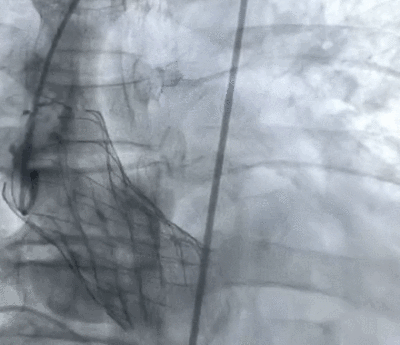

术后造影